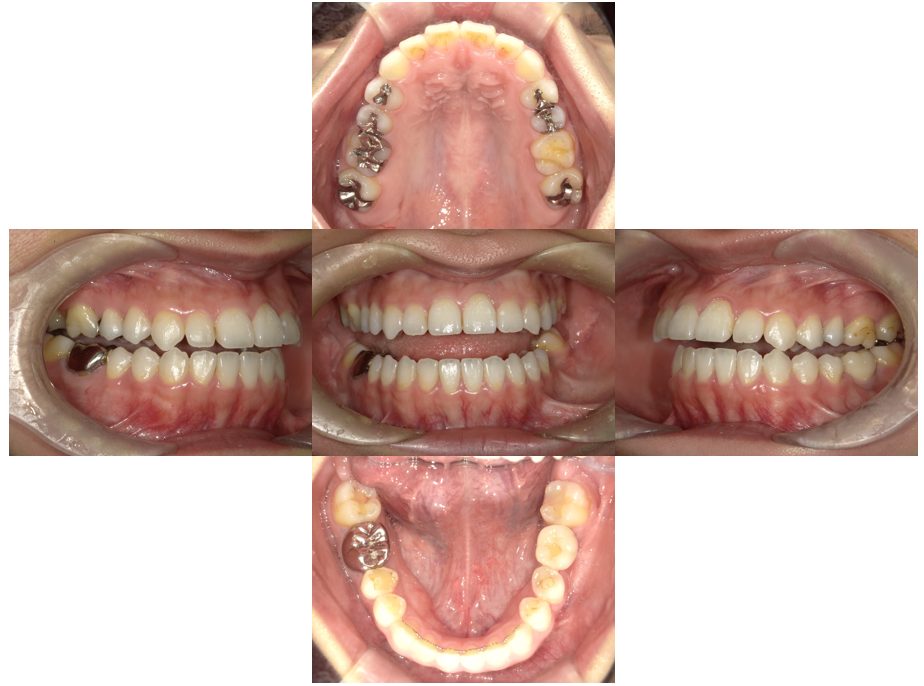

| 主訴 | 金属の詰め物が取れた、セラミックの治療希望 |

| 治療内容 | インプラント治療、セラミック治療、金属床コーヌス義歯(部分入れ歯)を行いました。 |

| 治療費 | 1,000,000円(税込み) |

| 治療期間 | 3か月 |

| 治療回数 | 20回 |

| 想定されたリスク | 残存歯の土台となる歯に変色がある場合は透けて見える可能性があった |